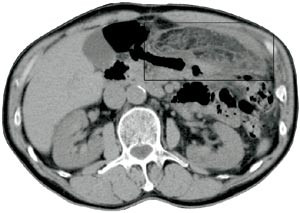

Pasient 1. En 56 år gammel mann med medikamentelt behandlet hypertensjon og tidligere operert brokk i epigastriet ble henvist fra primærlege til ultralydundersøkelse av abdomen på grunn av smerter under venstre costalbue, tiltakende over en uke og konstante de siste tre dager. Undersøkelsen viste en ekkorik, hovedsakelig homogen, 12 x 3 cm stor oval masse med enkelte lavekkogene avsnitt i sentrale deler og et tynt hypoekkoisk sjikt omkring (fig 1). Supplerende CT viste en 10 x 3 cm stor oppfylling i det tilsvarende området under venstre costalbue. Den lå tett an mot bukveggen foran ventrikkelen og hadde attenuasjon som fettvev med ødem (fig 2). Klinisk var han subfebril, direkte og indirekte øm medialt og nedenfor venstre costalbue, samt hadde forverring av smerten ved hoste. Man mistenkte omentnekrose, og pasienten ble operert ved laparoskopi. Alt nekrotisk vev ble resecert, og histologisk diagnose var fettvev med akutt hemoragisk infarkt og subserøs fibrose. Postoperativt forløp var ukomplisert.

Ultrasonografisk viser lesjonen seg som en rund eller oval ekkorik oppfylling lokalisert til ømhetens punctum maximum (1, 6) – (8). Oppfyllingen er ikke-komprimerbar og ofte adherent til peritoneum, sistnevnte demonstreres best i sagittalplan, hvor man under respirasjon kan observere lesjonens manglende bevegelighet i forhold til øvrig intraperitonealt innhold (7). Det ses ofte et 1 – 2 mm tynt, hypoekkoisk sjikt rundt oppfyllingen. Andre beskrevne assosierte funn er hypoekkoiske foci inni lesjonen som sannsynligvis representerer hemoragiske forandringer, fortykkelse av tilgrensende tarmvegg og peritoneum og masseeffekt med dislokasjon av tarm. Ved bruk av fargedoppler ses manglende blodstrøm.